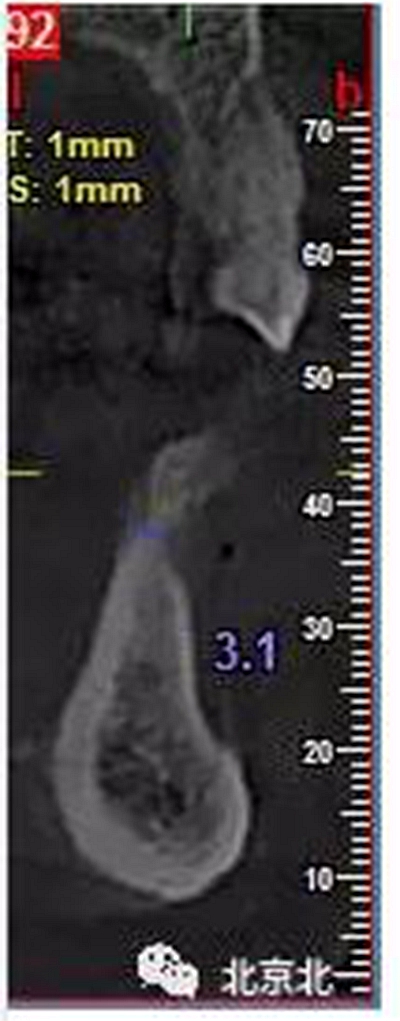

患者術(shù)前片, 最窄骨寬度僅僅3mm,34-35牙位缺失,

CBCT顯示如下圖